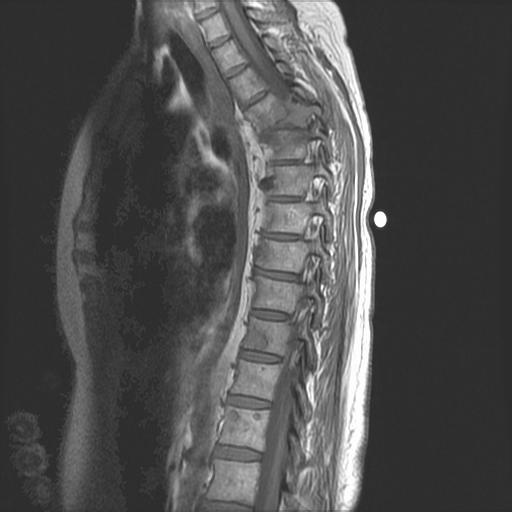

Myeloma Bone Disease

MRI (with contrast or STR images) very useful to delineate problems

MRI and FDG-PET in Multiple Myeloma

• > 3 focal lesions or SUV > 4.2 at diagnosis results in shorter PFS and OS[1]

• 65% of pts PET/CT negative 3 mos after ASCT with longer PFS and OS vs PET positive[1]

• Complete FDG suppression associated with durable disease control and prolonged OS[1]

• Skeletal survey recommended in cases of plasmacytoma, extramedullary disease, suspected spinal cord compression as well as with new symptoms or progression[2]

• MRI and/or PET/CT indicated when symptomatic areas show no abnormality on radiograph[3]

1. Zamagni E, et al. Blood. 2011;118:5989-5995. 2. Ludwig H, et al. Leukemia. 2014;28:981-992. 3. NCCN. Clinical practice guidelines in oncology: multiple myeloma. v.2.2014. 4. Boot M, et al. Novel prognostic modalities in multiple myeloma. 2013. MRI FDG PET Imaging Techniques[4]

PAIN PREVENTION AND MANAGEMENT

Pain can significantly compromise quality of life

Sources of pain include bone disease, neuropathy and medical procedures

Management

• Prevent pain when possible

• Bone strengtheners to decrease fracture risk; anti viral to prevent shingles; sedation before procedures

• Interventions depends on source of pain

• Monitor serum calcium levels

• Imaging may be needed depending on type and location of pain (eg, MRI, PET-CT)

• May include medications (eg bone modifying agents), activity, surgical intervention, radiation therapy, etc